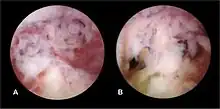

The history of a pregnancy event followed by a D&C leading to secondary amenorrhea or hypomenorrhea is typical. Hysteroscopy is the gold standard for diagnosis.[18] Imaging by sonohysterography or hysterosalpingography will reveal the extent of the scar formation. Ultrasound is not a reliable method of diagnosing Asherman's Syndrome. Hormone studies show normal levels consistent with reproductive function.

Fertility may sometimes be restored by removal of adhesions, depending on the severity of the initial trauma and other individual patient factors. Operative hysteroscopy is used for visual inspection of the uterine cavity during adhesion dissection (adhesiolysis). However, hysteroscopy is yet to become a routine gynaecological procedure and only 15% of US gynecologists perform office hysteroscopy.[32] Adhesion dissection can be technically difficult and must be performed with care in order to not create new scars and further exacerbate the condition. In more severe cases, adjunctive measures such as laparoscopy are used in conjunction with hysteroscopy as a protective measure against uterine perforation. Microscissors are usually used to cut adhesions. Electrocauterization is not recommended.[33]